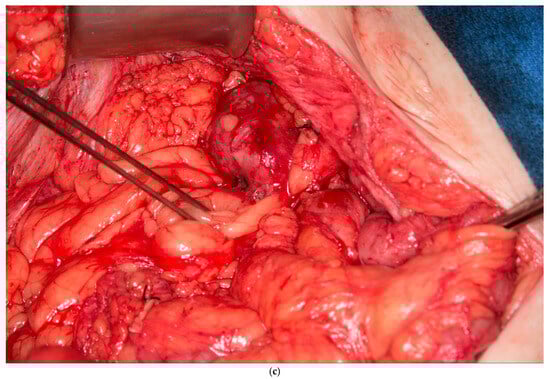

3.2. Peritoneal, Preperitoneal Fat and Falciform Ligament Flap

This patient had no greater omentum left, as it was removed during a previous total abdominal colectomy. A VRAM was also not possible because she had bilateral rectus abdominus divisions from transverse incisions as a child, and no perforators to the skin could be identified. However, she had some remaining deep perforating branches of the inferior epigastric artery. She required a proctectomy because of a rectovaginal fistula and anal stenosis. Once the midline laparotomy incision was made with the assistance of a plastic surgeon, the peritoneum and preperitoneal fat were dissected off her posterior sheath bilaterally (See Figure 3a,b). The falciform ligament was ligated, divided as high as possible, and kept in continuity with the peritoneum and peritoneal fat flap. A persistent branch of the deep inferior epigastric vessel supplying this tissue was identified and protected. The peritoneum was also mobilized off the lower aspect of the rectus muscle to allow the flap to be advanced toward the pelvis. Doppler ultrasonography was used to confirm that blood supply to the flap was maintained. The flap was then secured to the pelvic inlet in a sling-like fashion to keep the small intestine out of the pelvis (See Figure 3c). A 19 Fr drain was placed in the pelvis at the end of the case.

Figure 3.

(a) Peritoneum and preperitoneal fat dissected off the patient’s left posterior sheath. (Used with permission from the Mayo Foundation for Medical Education and Research; all rights reserved). (b) Peritoneum, preperitoneal fat, and falciform ligament dissected off the patient’s right posterior sheath. (Used with permission from the Mayo Foundation for Medical Education and Research; all rights reserved). (c) Bilateral pedicled flaps sutured to the pelvic inlet, creating a sling to prevent a small bowel from falling into the pelvis. (Used with permission from the Mayo Foundation for Medical Education and Research; all rights reserved).